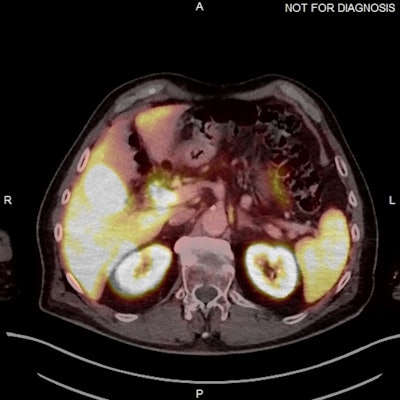

(Above) Fused axial image demonstrates uptake in the celiac ganglia. (Below) Corresponding CT scan. The celiac ganglia are visible. All figures courtesy of Dr. Jonathan Hunter, Dr. Jane Burns, and Prof. Martin O’Connell and presented at ECR 2025.

The physiological uptake of PSMA ligands in various normal tissues is an important pitfall in PSMA-targeted imaging, they continued. In particular, uptake in sympathetic trunk ganglia can pose challenges to nuclear medicine readers and may mimic lymph nodes. Also, cervical chain and coeliac ganglia may demonstrate higher uptake with F-18 PSMA.